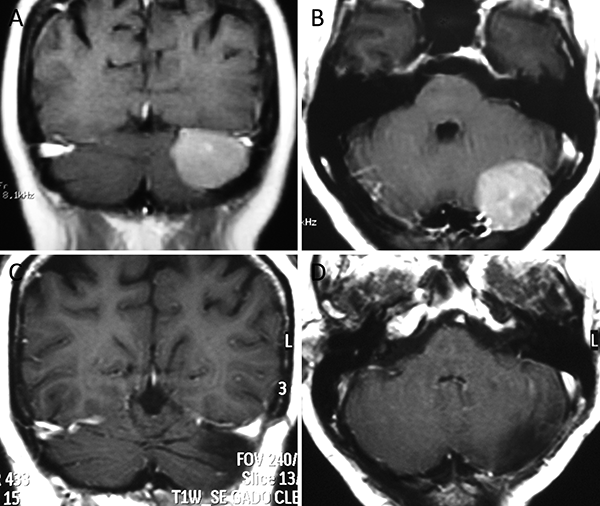

Figura 1. Meningioma tentorial medial. A-B: RM preoperatoria; C-D: RM postoperatoria.